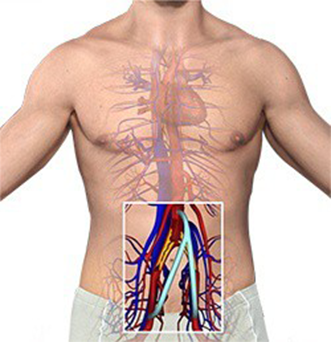

Cirurgia de Aneurisma de Aorta

Chamamos de aneurisma de aorta, a dilatação exagerada deste vaso. A doença pode acometer qualquer porção da aorta, desde sua saída do coração, até seu final, à altura do umbigo. Os aneurismas de aorta mais frequentes estão localizados no abdome, especialmente abaixo das artérias renais. Há basicamente duas formas de correção a fim de evitar a ruptura do aneurisma: a cirurgia e a correção endovascular com implante de uma endoprótese (assista ao vídeo). Na cirurgia para correção do aneurisma de aorta abdominal, com anestesia geral, o abdome é aberto pelo cirurgião vascular e o segmento dilatado da aorta é substituído por uma prótese tubular artificial, que se integra perfeitamente ao paciente.

Cirurgia de Aneurismas Periféricos

Assim como na aorta, os aneurismas podem acometer outras artérias do corpo humano. Nos membros inferiores, o aneurisma mais frequente é o que acomete a artéria poplítea, localizada atrás da articulação do joelho. Os aneurismas também podem acometer vasos viscerais como artérias esplênicas, mesentéricas ou renais. O problema pode ser solucionado tanto por técnica endovascular como por cirurgia, de acordo com as características de cada caso.